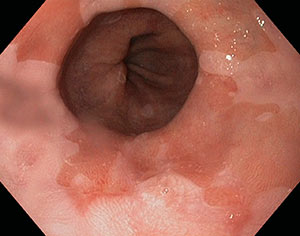

Esofago di Barrett

È considerata una lesione precancerosa, in quanto è una complicanza patologica della esofagite cronica dovuta alla sostituzione progressiva della mucosa distale dell'esofago con la mucosa gastrica (metaplasia) in risposta a prolungati stimoli lesivi. Tale condizione può evolvere in displasia lieve (ossia alterata crescita tessutale), poi in displasia grave e poi ancora in cancro in situ.

Esofagogastroduodenoscopia con biopsie della mucosa esofagea